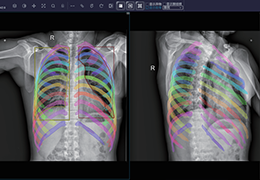

成像智能。

Eclipse 成像智能功能提供强大的处理能力和最佳质量的影像,同时减少质量错误并提高剂量效率。

凭借 AI、专有算法和先进的影像处理能力,提供出色的影像质量和无与伦比的诊断信心。

与标准影像处理相比,智能降噪功能可使客户降低辐射剂量,而不会损失影像质量。这在新生儿和儿科成像中尤其重要,在这种情况下以尽可能低的剂量成像至关重要。

提供相配视图选项,以减少所需的曝光次数,并提供更清晰的感兴趣区域视图。